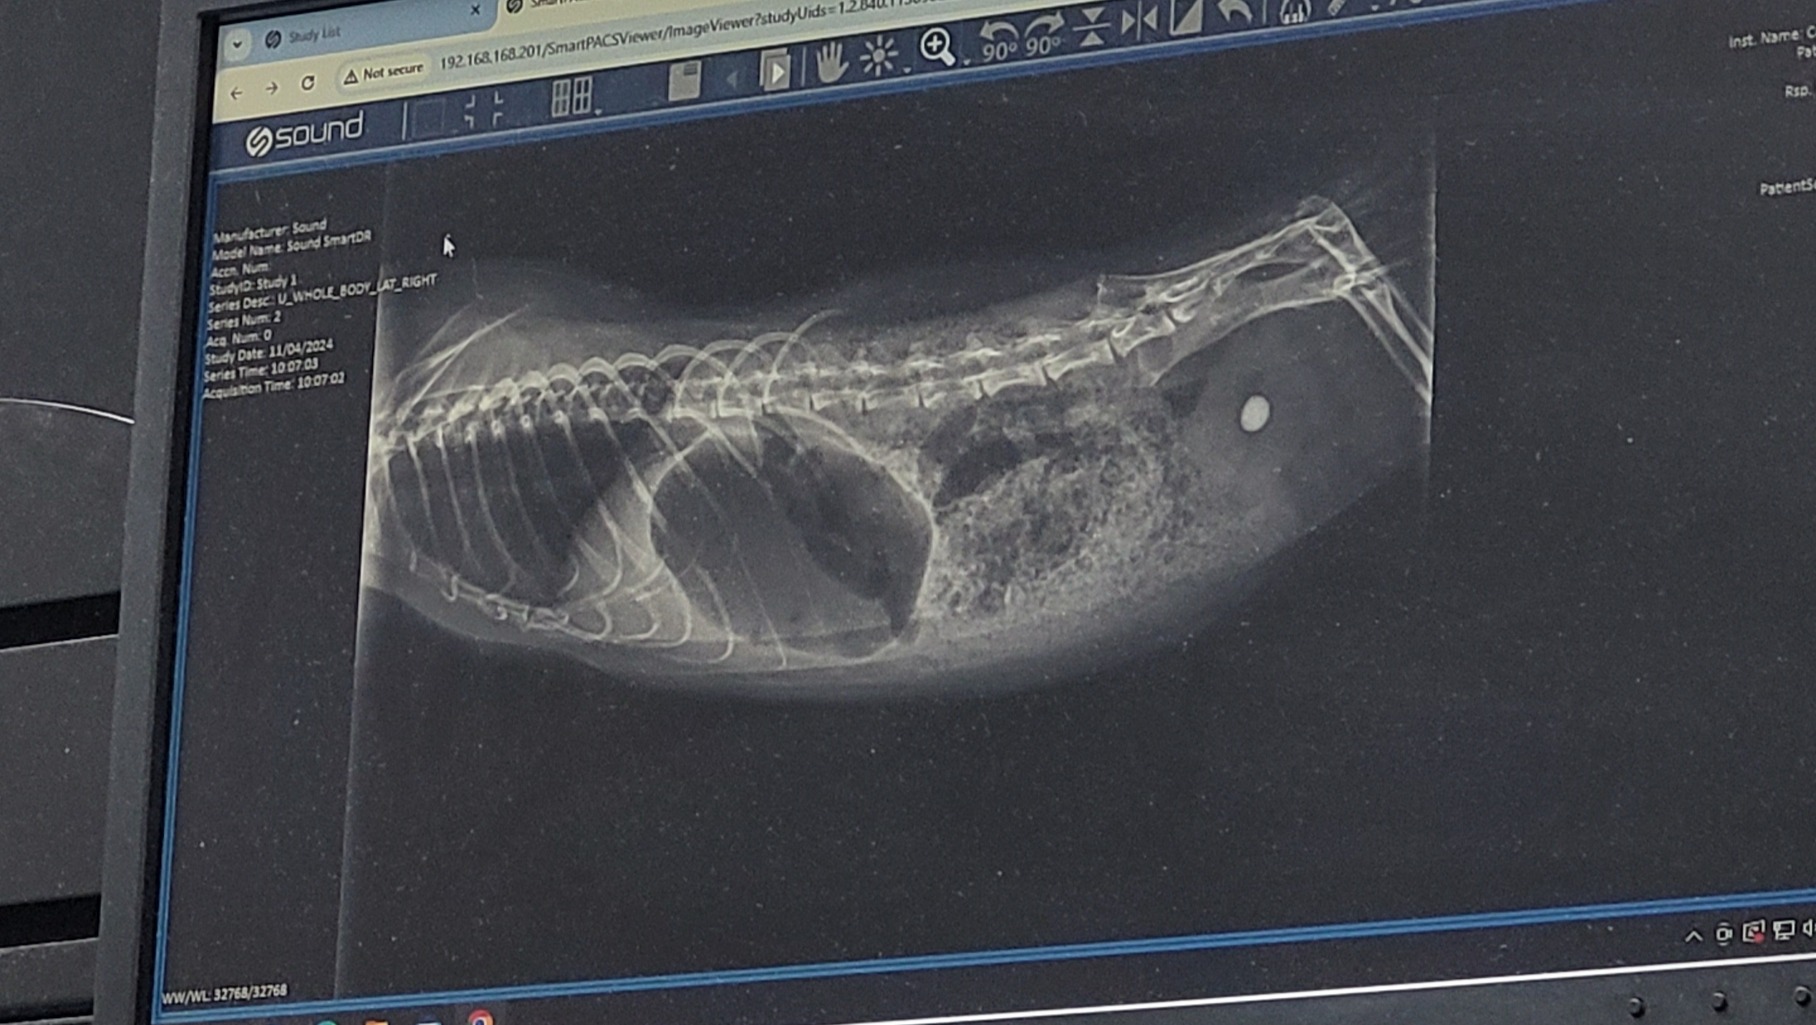

Hello family and friends, I'm raising money for my guinea pig Gizmo who's at risk of dying, due to a bladder stone. He's peeing blood and squealing in pain and is not the same happy/healthy piggy he was before. If you're an animal lover like me, you can understand how vulnerable I am to save his life. Absolutely anything can help. I know times are tough, thoughts and prayers are also appreciated. If you can please help me reach my goal to save my baby I would greatly appreciate it whole heartedly. Our other piggy Chopper would also appreciate your efforts to save his brother :)